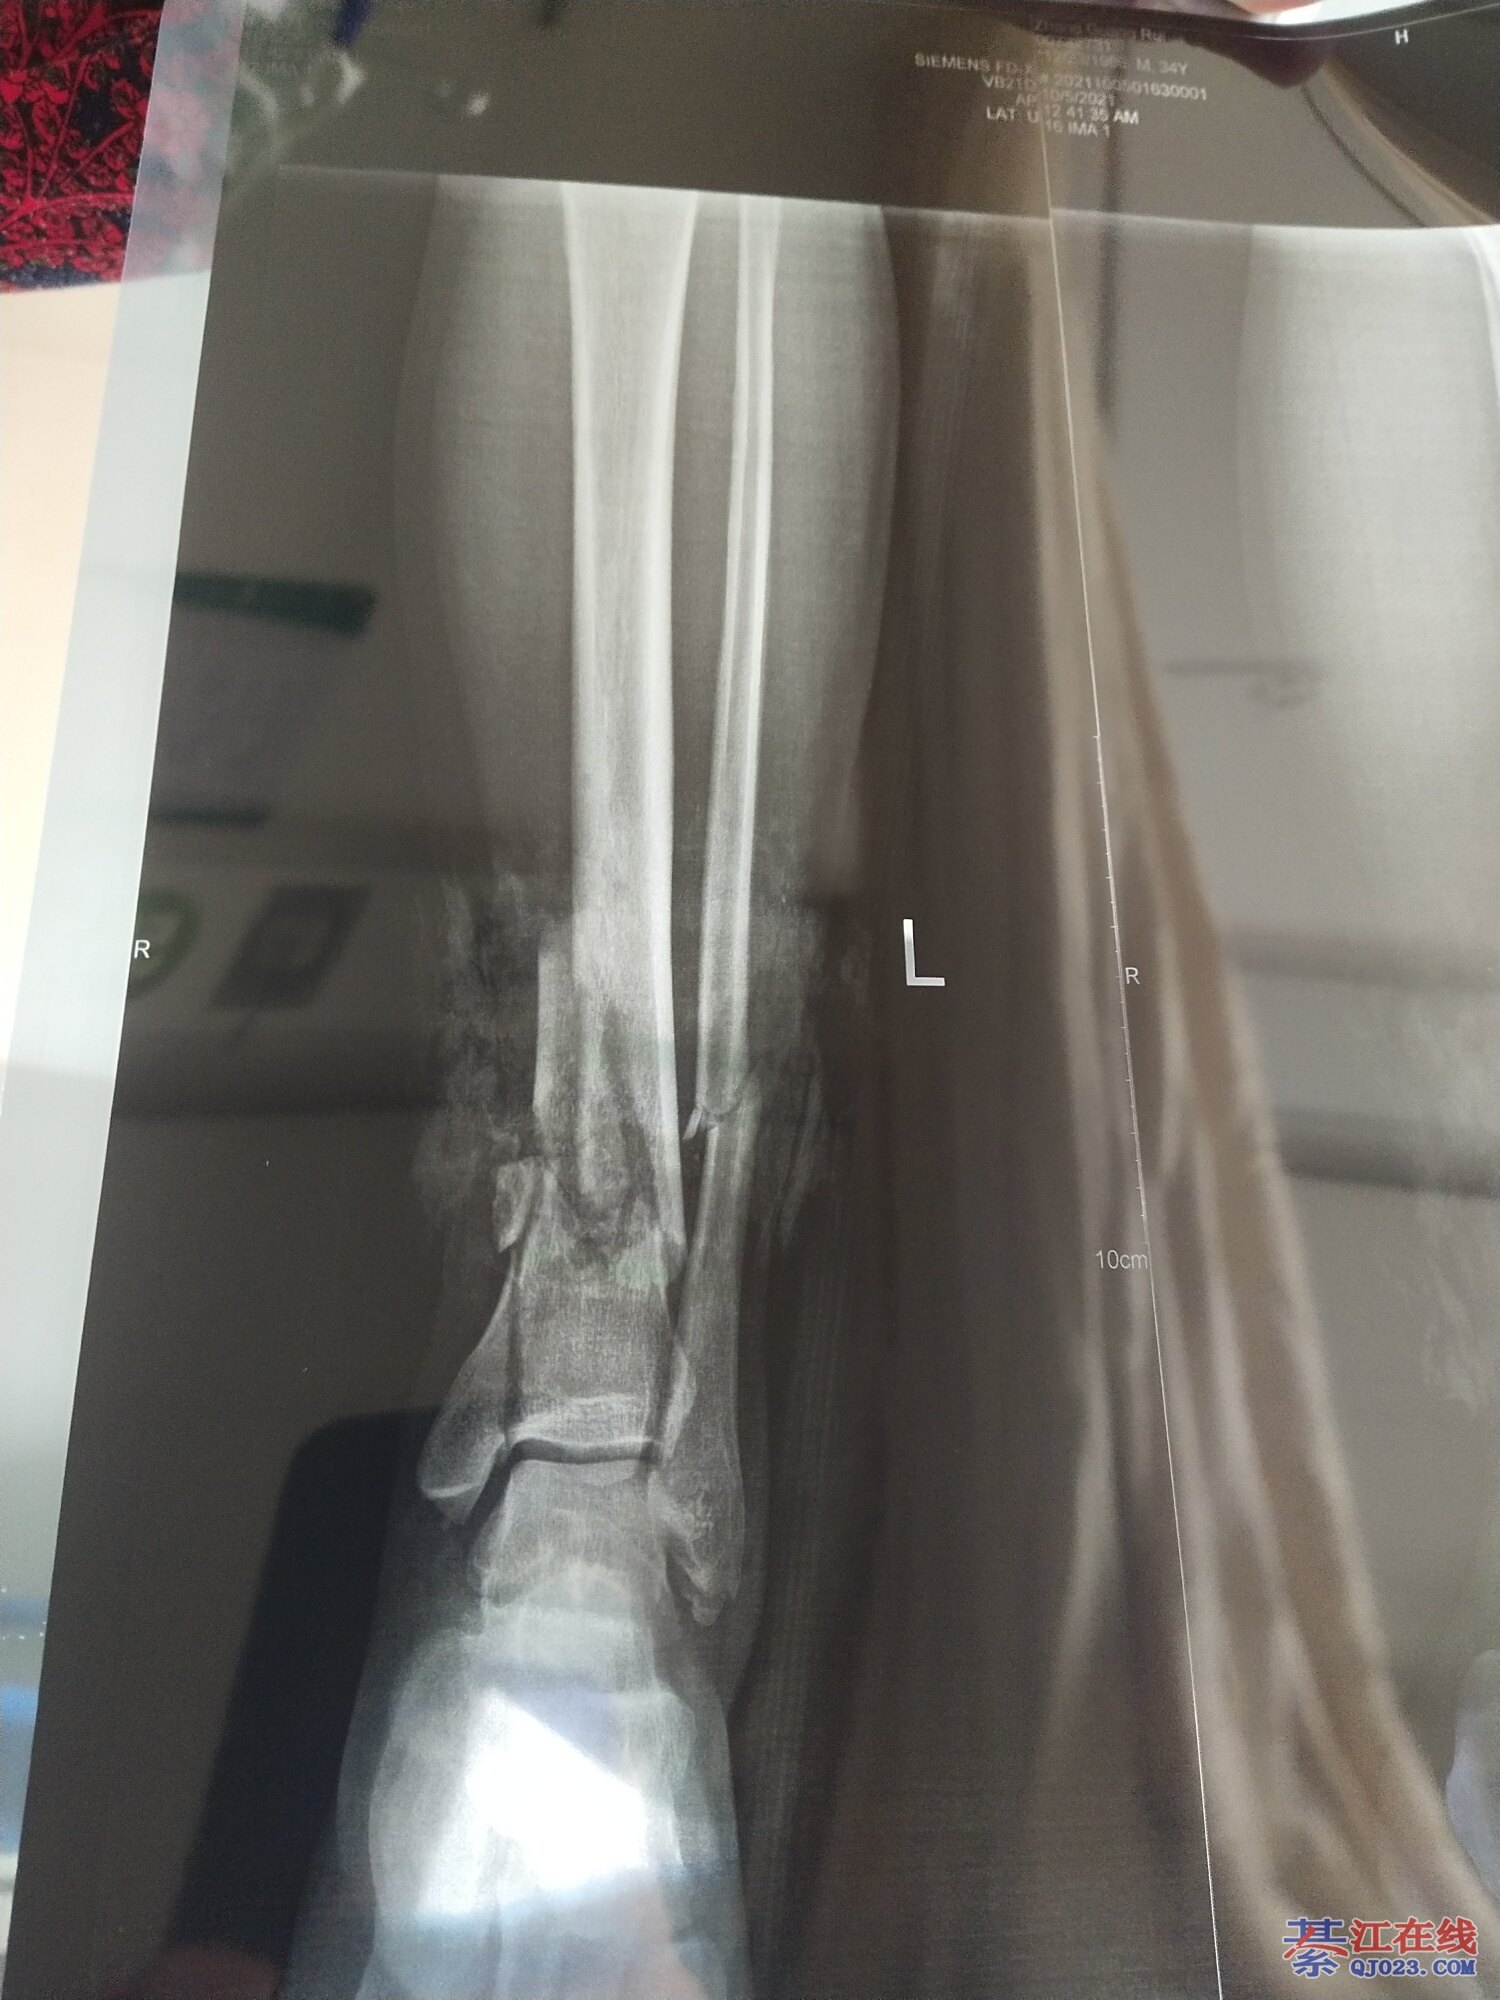

看到都疼,祝早日康复